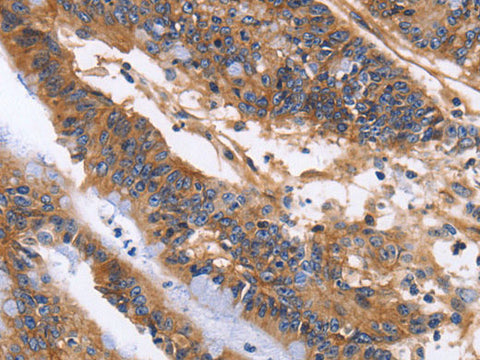

Applications WB,  IHC

IHC 1:50-1:200